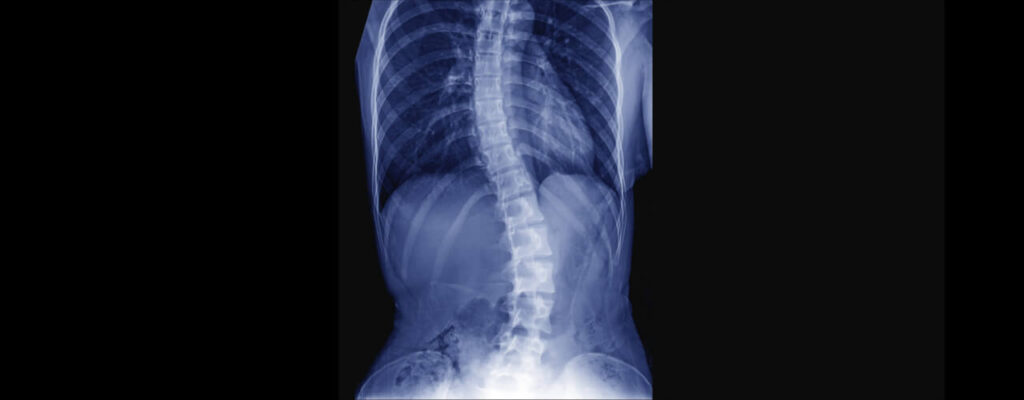

Back Pain And Sciatica

According to the American Physical Therapy Association, back pain is the most…